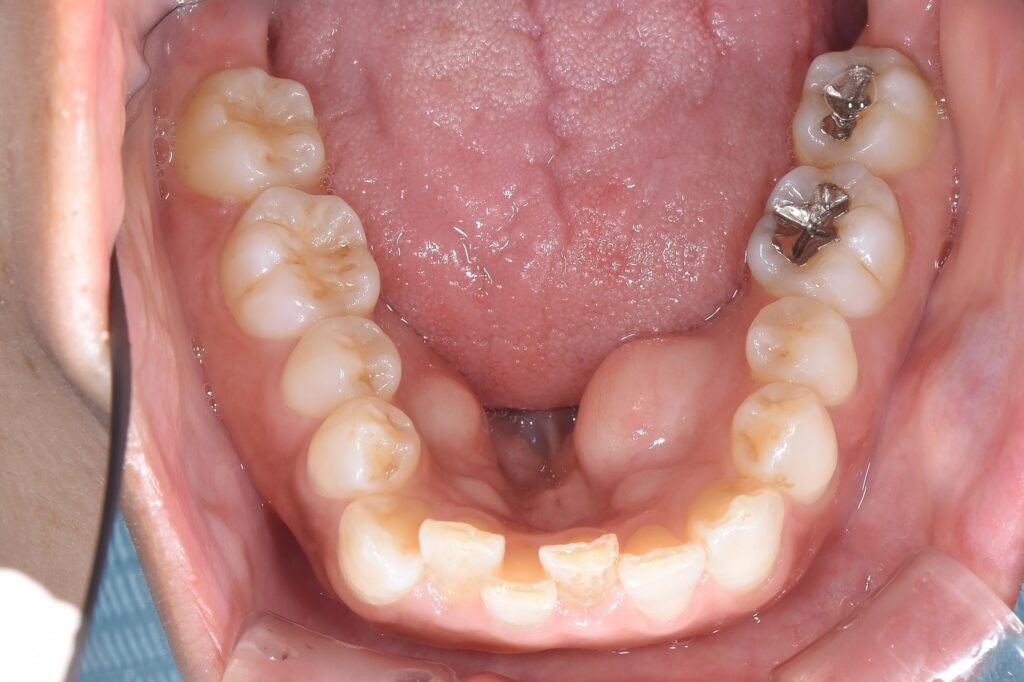

【初診時の状態】

上前歯2本が他院で仮歯を装着して頂いていたが、外れそうとのことで受診されました。検査の結果、虫歯でどうしても残すことが困難な状態でした。相談の上、治療終了時に長持ちする治療を希望され、矯正治療行い、その後前歯にセラミック治療を行うことになりました。以下に治療終了時の状態です。

上顎のお悩みの歯だけを施術する場合、下顎の歯にがたつきが存在すれば、上の歯もがたつきが出てしまいます。理想的な美しい状態にするのは困難を極めます。矯正治療が可能であれば、問題は解決できます。